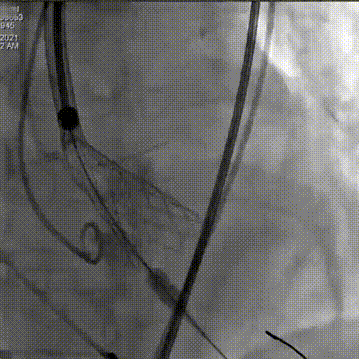

重心定位后,第二次释放到瓣膜工作位,发现LCA灌注缝隙狭小

预置LCA保护

完全回收,第三次定位释放,瓣膜位置良好

瓣膜工作位释放“烟囱支架”